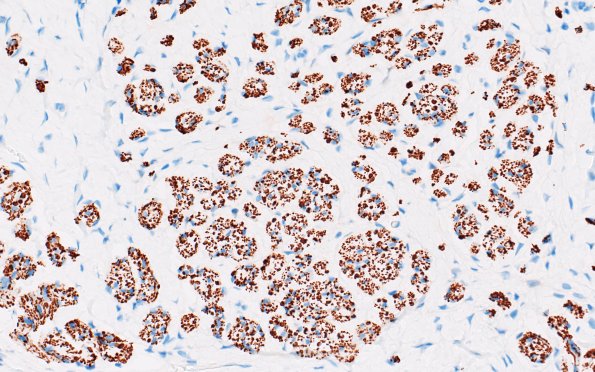

23B4 Neuroma (Case 23) NF 40X

Higher magnification of mini-fascicles in longitudinal (23B3) and cross sections (23B4,5). (NF IHC)